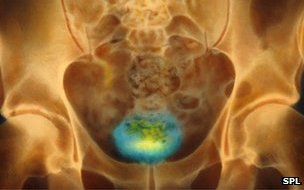

Brit kutatók kifejlesztettek egy készüléket, amely gerincsérülteknek segíthet a hólyag irányításában.

Az idegrendszer károsodása miatt egyes betegek nem érzékelik, mikor van tele a hólyagjuk, és irányítani sem tudják az ürítést, mivel megszakadt az idegi kommunikáció az agy és a húgyhólyag között.

Egy új eszköz "leolvassa" az épen maradt idegsejtek jeleit, ezzel képes lehet irányítani a szervet - tudósított a BBC News a Science Translational Medicine című szaklapban megjelent tanulmányról.

A Cambridge-i Egyetem kutatói olyan megoldást találtak, amely a hólyag körüli idegsejtek használatára alapul. Az idegsejt-csoportok köré illesztett elektródák közvetíteni tudják a hólyag telítettségéről tudósító jelzéseket. Ha más idegcsoportokat stimulálnak, akkor a hólyag a beteg igénye szerint működhet ahelyett, hogy magától ürülne.

A készülék patkányok esetében működött, már csak a teljes technológia miniatürizálása van hátra - mondta el Daniel Chew, a kutatók egyike a BBC-nek. A patkány szervezetébe ültetett alkatrészeket át lehet alakítani emberi használatra, az információ feldolgozásához szükséges további eszköz azonban egy kétméteres készülékoszlop, amelyet akkorára kell kicsinyíteni, hogy elférjen a páciens kezében. A kis hordozható eszköz a jövőben jelezheti a betegnek, amikor megtelt a hólyag, egy gomb megnyomásával pedig kiválthatja a hólyag összehúzódását, vagyis az ürítést.